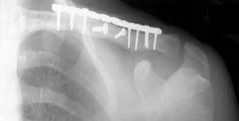

Figure 3a Figure 3b Figure 3c Figure 3a is the initial radiograph of a 19-year-old man who sustained a closed clavicle fracture. Figures 3b and 3c show postoperative radiographs. If the patient had been treated nonsurgically, which of the following would most likely occur?